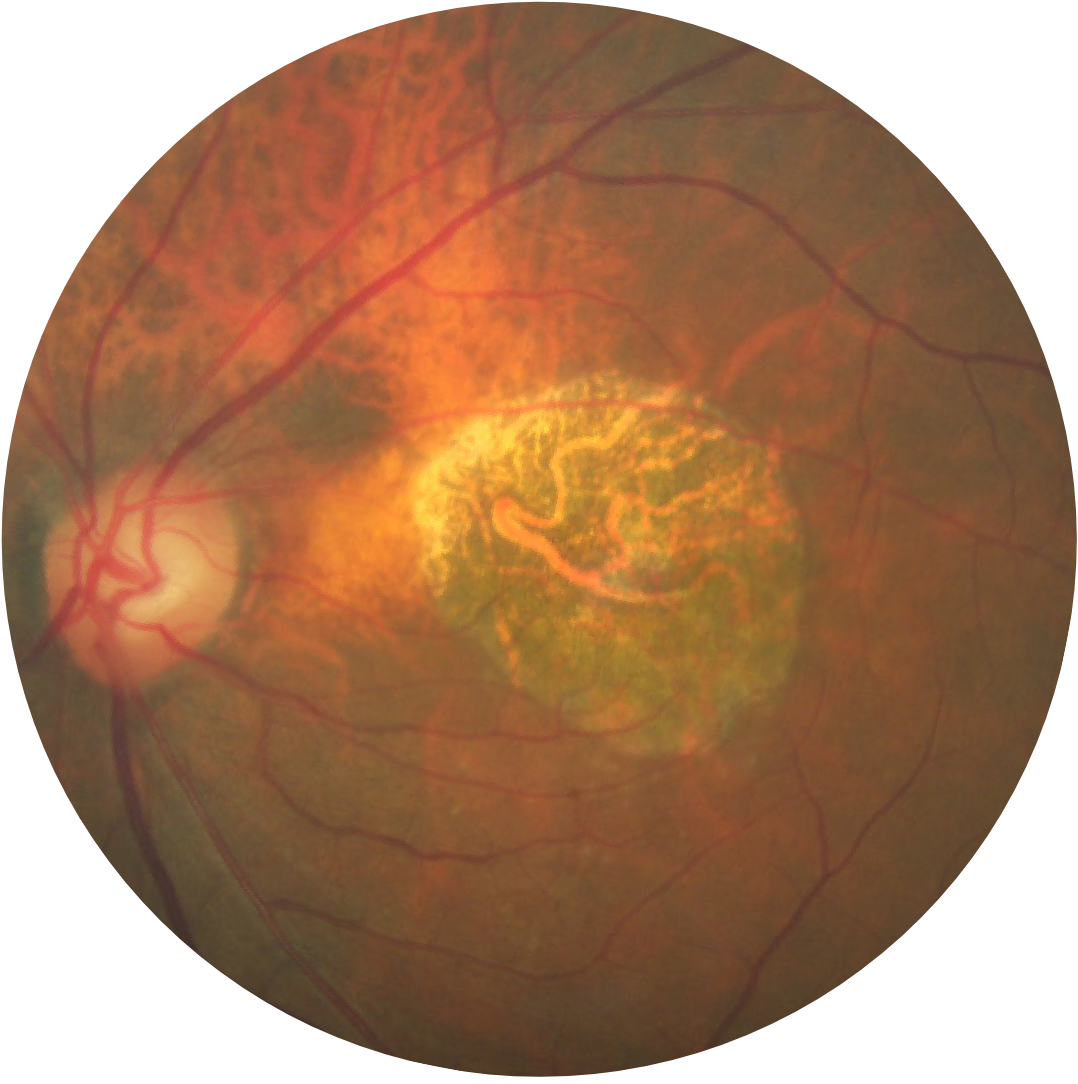

Fotografia del fondo oculare di un occhio con atrofia geografica

L’atrofia geografica è caratterizzata da una perdita progressiva e irreversibile dei fotorecettori, dell’epitelio pigmentato retinico (EPR) e della lamina coriocapillare sottostante.1,2

Le regioni di atrofia iniziano solitamente al di fuori della fovea e si espandono fino a coinvolgere la fovea, il che, nel tempo, porta alla perdita permanente della vista.1

• Area nettamente demarcata nella regione maculare con retina atrofica, priva di pigmentazione

• Vasi sanguigni coroidali sottostanti visibili